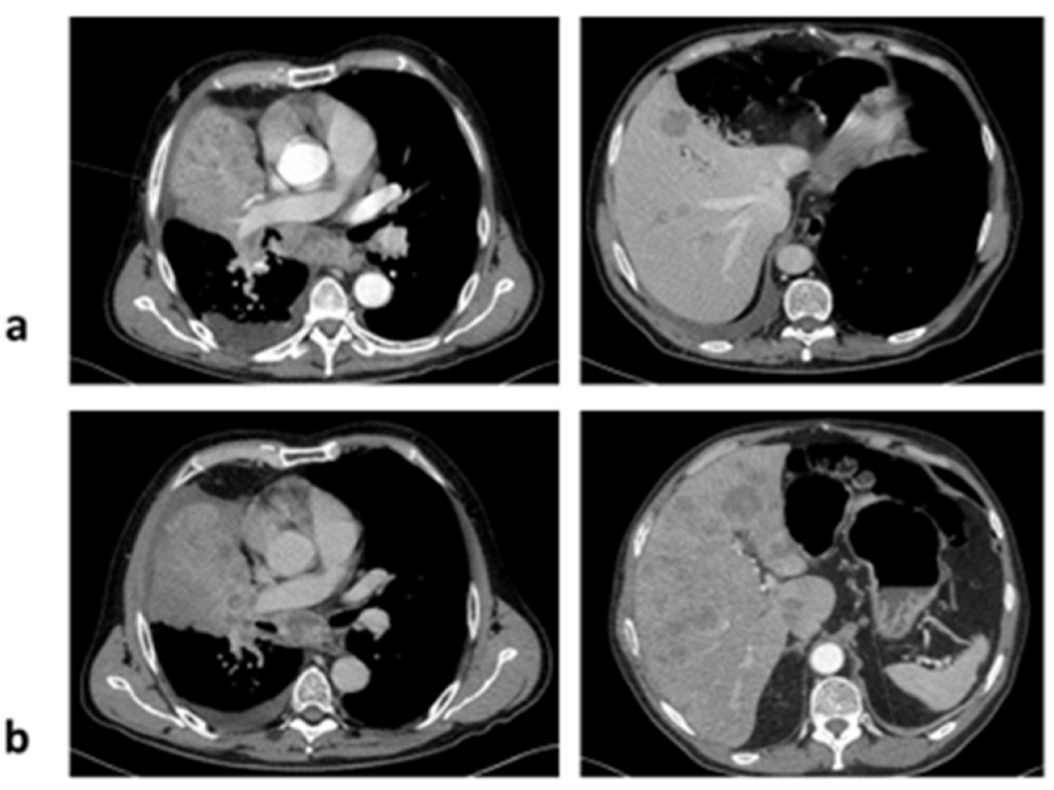

2. Case 1